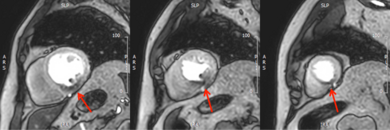

Auf Grund der hohen räumlichen und zeitlichen Auflösung sowie der hervorragenden Gewebedarstellung können mittels kardialer MRT sowohl die Gewebezusammensetzung als auch Funktion aller Herz - und Gefäßanteile exzellent mit hoher Genauigkeit dargestellt und charakterisiert werden. Als nicht-invasives Verfahren, welches ohne ionisierende Strahlung (Röntgenstrahlung) auskommt, ist die kardiale MRT zudem ein äußerst sicheres Verfahren, das auch mehrfache Verlaufsuntersuchungen – beispielsweise bei Herzmuskelerkrankungen – erlaubt. Sie bietet darüber hinaus gegenüber anderen Bildgebungsmodalitäten den Vorteil, das Gewebe des Herzens nicht-invasiv charakterisieren zu können, was sonst nur mittels histologischer Analysen nach Biopsieentnahme möglich wäre. Diese „Gewebecharakterisierung“ erfolgt einerseits mittels spezieller Late Gadolinium Enhancement-Aufnahmen, bei denen die Patient*innen ein gut verträgliches MRT-Kontrastmittel erhalten und andererseits mittels moderner Mapping-Techniken, welche größtenteils ohne Kontrastmittelapplikation auskommen. Durch diese Techniken können Fibrose, Narben (z.B. nach Herzinfarkt) oder Wassereinlagerungen (Ödem) im Herzmuskel festgestellt werden.

Ein weiterer wichtiger Aufgabenbereich der kardialen MRT stellt die Diagnostik und Risikostratifizierungen von primären Herzmuskelerkrankungen (Kardiomyopathien) dar. Neben der Beurteilung der Funktion und Struktur des Herzens ist dabei die Gewebecharakterisierung von herausragender Bedeutung, da insbesondere die Patient*innen, bei denen Vernarbungen und Fibrose im Herzmuskel nachgewiesen werden kann, ein erhöhtes Risiko aufweisen.

Weiter wesentliche Schwerpunkte der kardialen MRT sind die Erkennung von entzündlichen Veränderungen im Herzmuskel (z.B. Myokarditis), die Differenzierung von Speichererkrankungen des Herzens (z.B. Amyloidose), Verlaufskontrolle der Herzfunktion unter Chemotherapie bis hin zu komplexen angeborenen Herzfehlern. Mittlerweile können auch Herzklappenfehler und intrakardiale Shunts exakt mit der kardialen MRT ausgemessen werden.